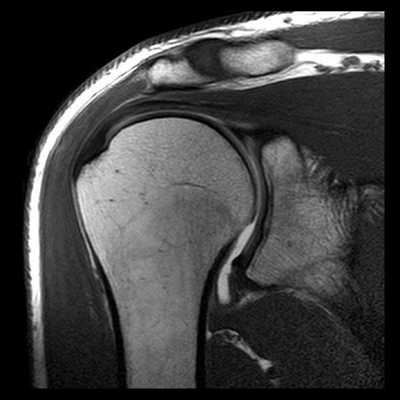

(Справа) На фронтальной МРТ Т2ВИ FS после вывиха предплечья определяется разрыв переднего пучка локтевой коллатеральной связки с отрывом выступающего бугорка и разрывом кольцевой и лучевой коллатеральной связки и латеральной локтевой коллатеральной связки. (Слева) На передне-задней рентгенограмме ребенка определяется полное смещение дистального эпифиза плечевой кости от дистальной трети диафиза плечевой кости. Чтобы отличить его от вывиха плеча, следует обратить внимание на сохранение нормального расположения луче-головчатого и локтеблокового суставов.

4. МРТ при вывихе предплечья:

• Информативна для характеристики сопутствующего повреждения связок:

о Латеральная локтевая коллатеральная связка

о Лучевая коллатеральная связка

о Локтевая коллатеральная связка

• Помогает выявить костно-хрящевые дефекты:

о Чаще встречаются в случае отсроченного вправления